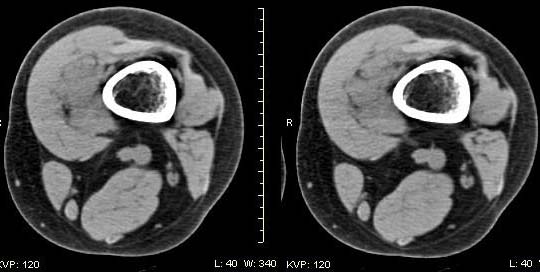

女,24岁,左大腿下部近膝关节处偏内侧有一软组织包块,触之有压痛,平扫示病灶密度不均,形态及轮廓欠规则,无包膜,与周围组织界限不清,增强后显示有明显强化且不均匀强化,本人考虑为该软组织肿块为恶性病变。请大家发表高见!

病理结果:血管瘤。

血管瘤,增强延迟扫描。